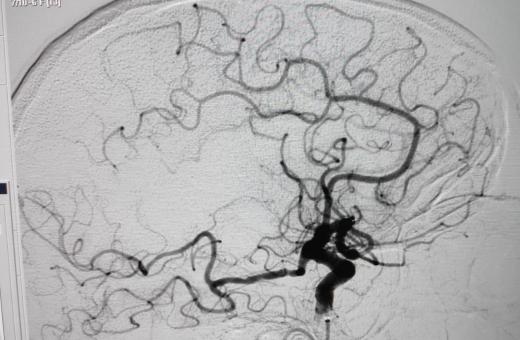

02/02/2021 L’Hospital Trueta posa en marxa una nova Unitat d’Ictus, amb habitacions adaptades pel tractament precoç dels pacients que han patit un infart o una hemorràgia cerebral